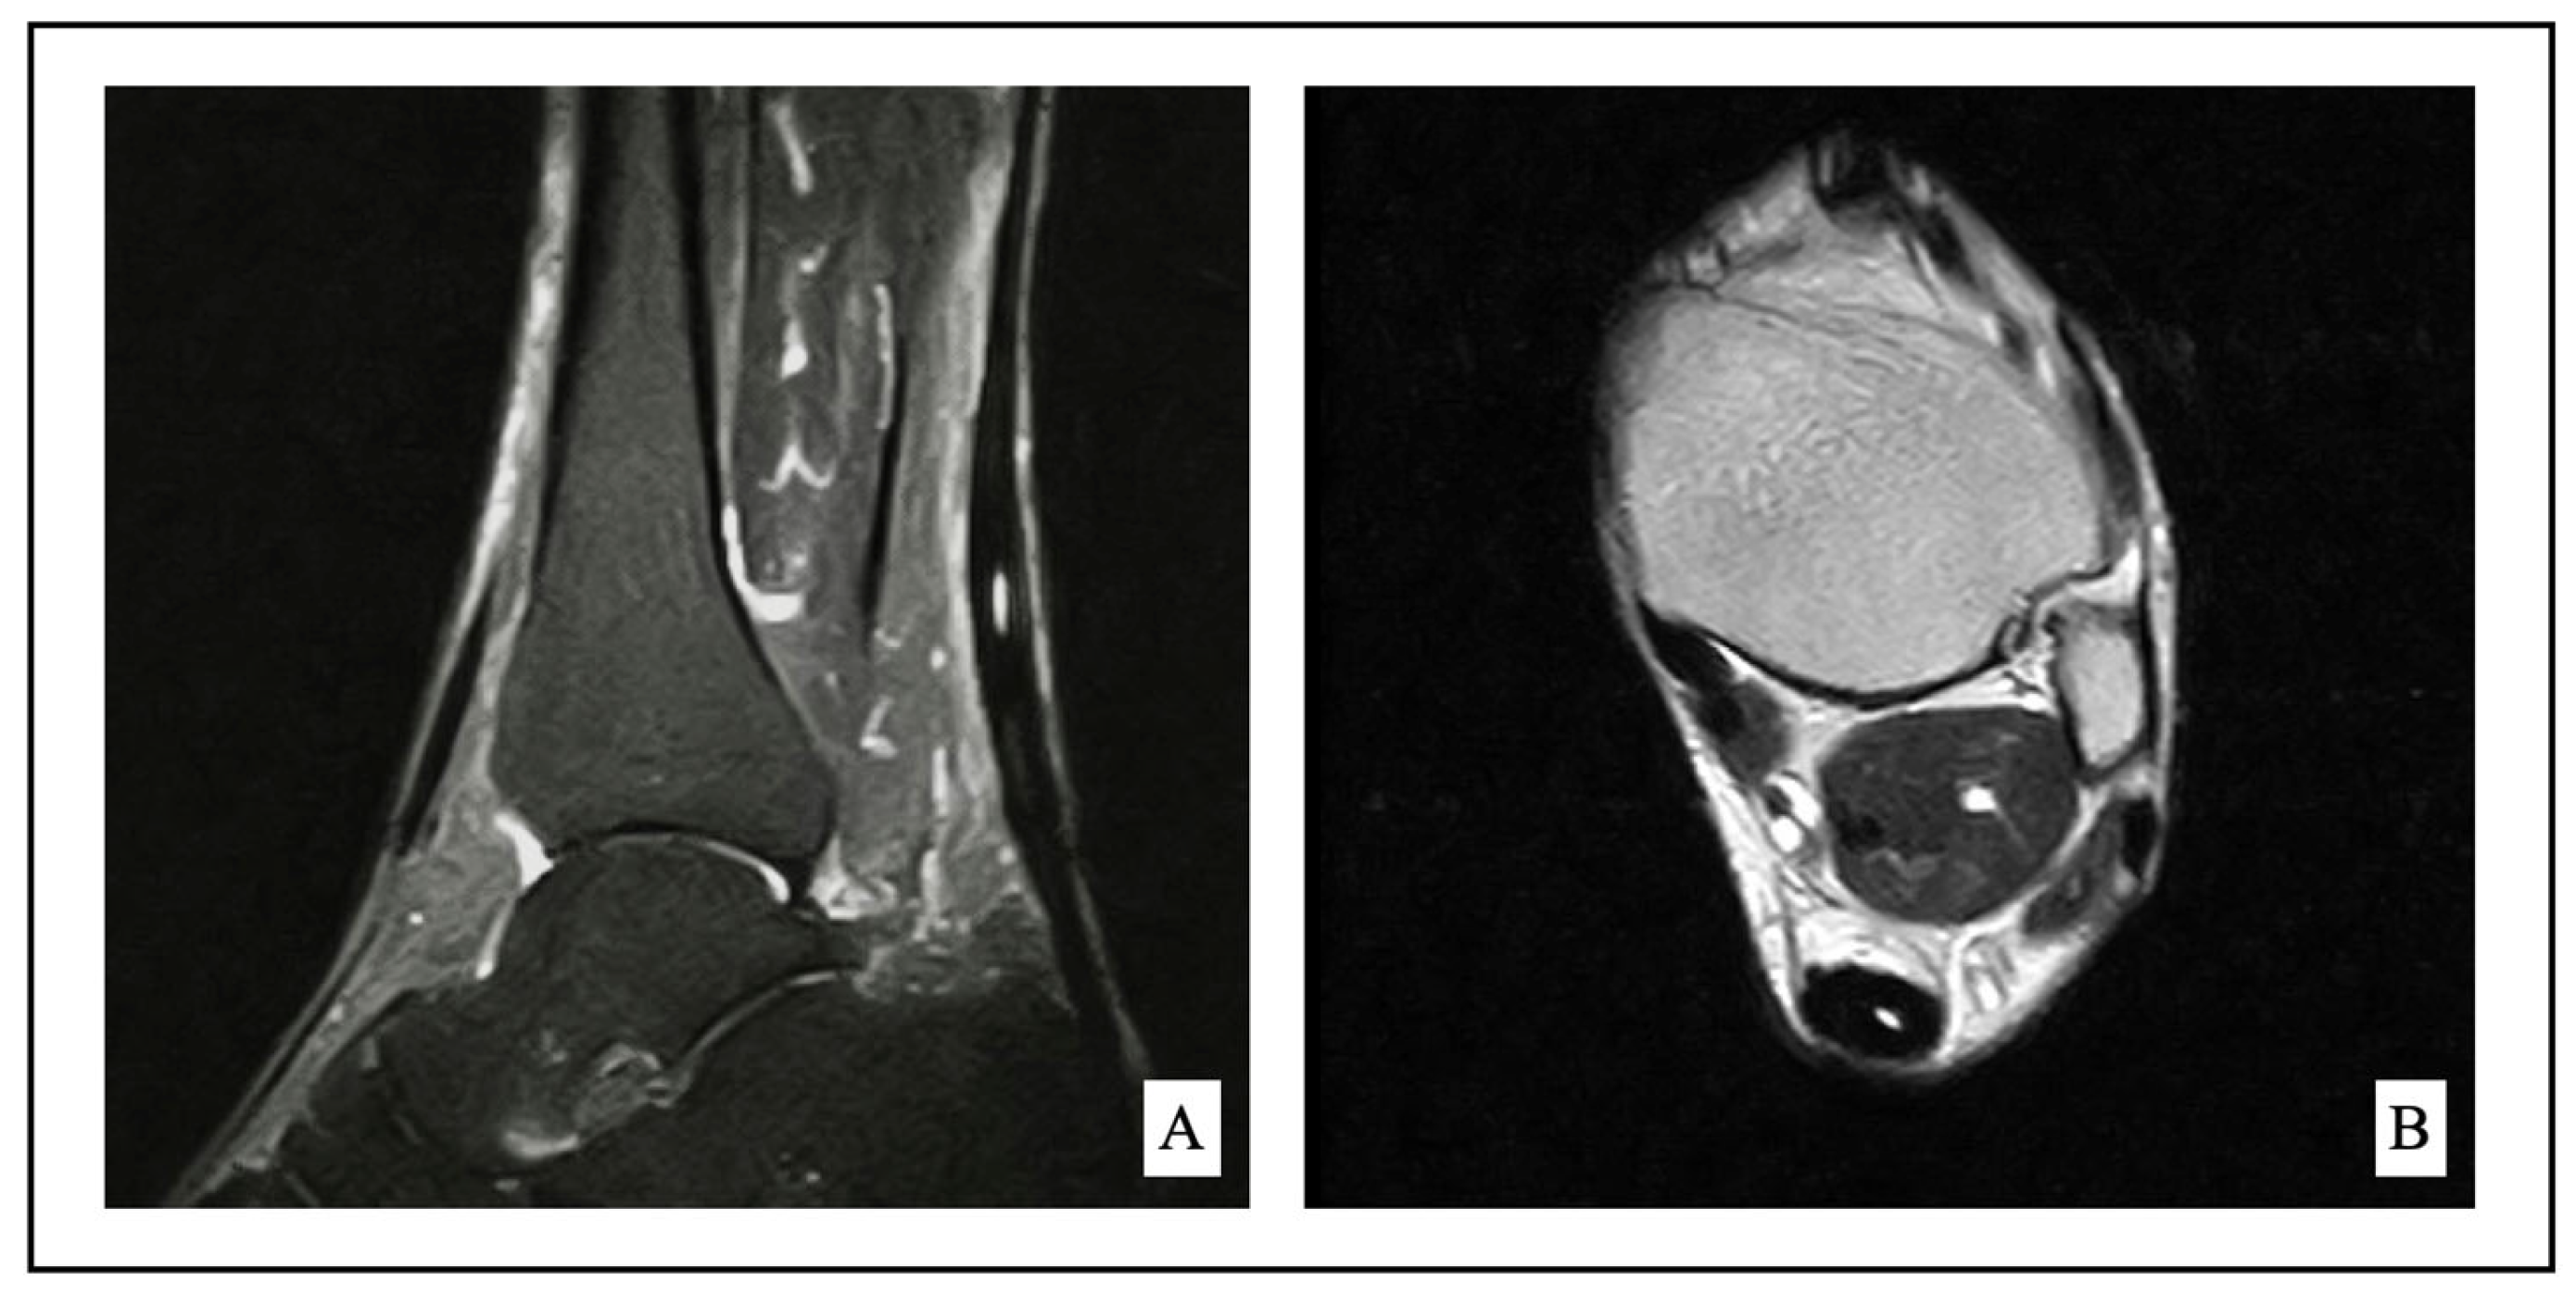

2.2. Indication for Surgery

2.4. Surgical Technique